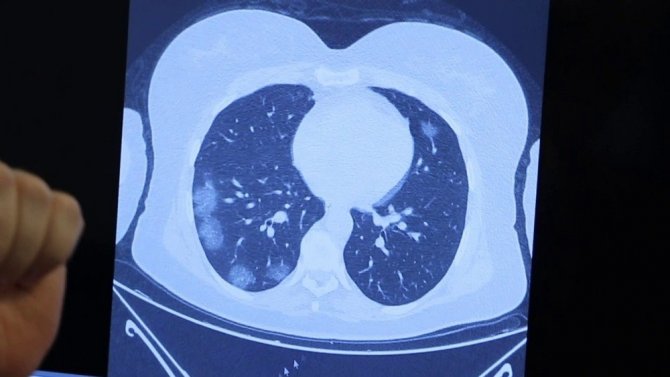

Korona geçirmiş bir ailenin akciğer tomografilerini inceleyen Prof. Dr. Özkaya, "Bir örnek vermek gerekirse, bu genç hastamız 26 yaşında, ailede ilk kez bu çocuk pozitif oluyor. Genç olduğu için hafif atlatıyor. Sonra annesini enfekte ediyor. Annesi çocuktan bir tık daha fazla akciğer tutulumuyla geliyor. Daha sonra da babası enfekte oluyor. Annesini tedavi ettik ama babası inanılmaz solunum yetmezliğiyle bize başvurdu. Yani virüs "akıllı bir organizma" gibi davranıyor. Ailede birini enfekte ettiği zaman diğer enfekte edeceği kişide bir tık daha kötü akciğer hasarı yapıyor. Bu konuda vatandaşlarımızın mutlaka aile içindeki temasa çok dikkat etmesi lazım. Virüs 2019'da bulundu, 2020'de salgın ilan edildi, hastalığın 2021'de daha kötü bir tabloya yol açmaması için herkesin dikkat etmesini ve aşı konusunda da duyarlı olmasını istiyoruz. Çünkü tek kurtuluşumuz şu an aşı gibi duruyor" şeklinde konuştu.